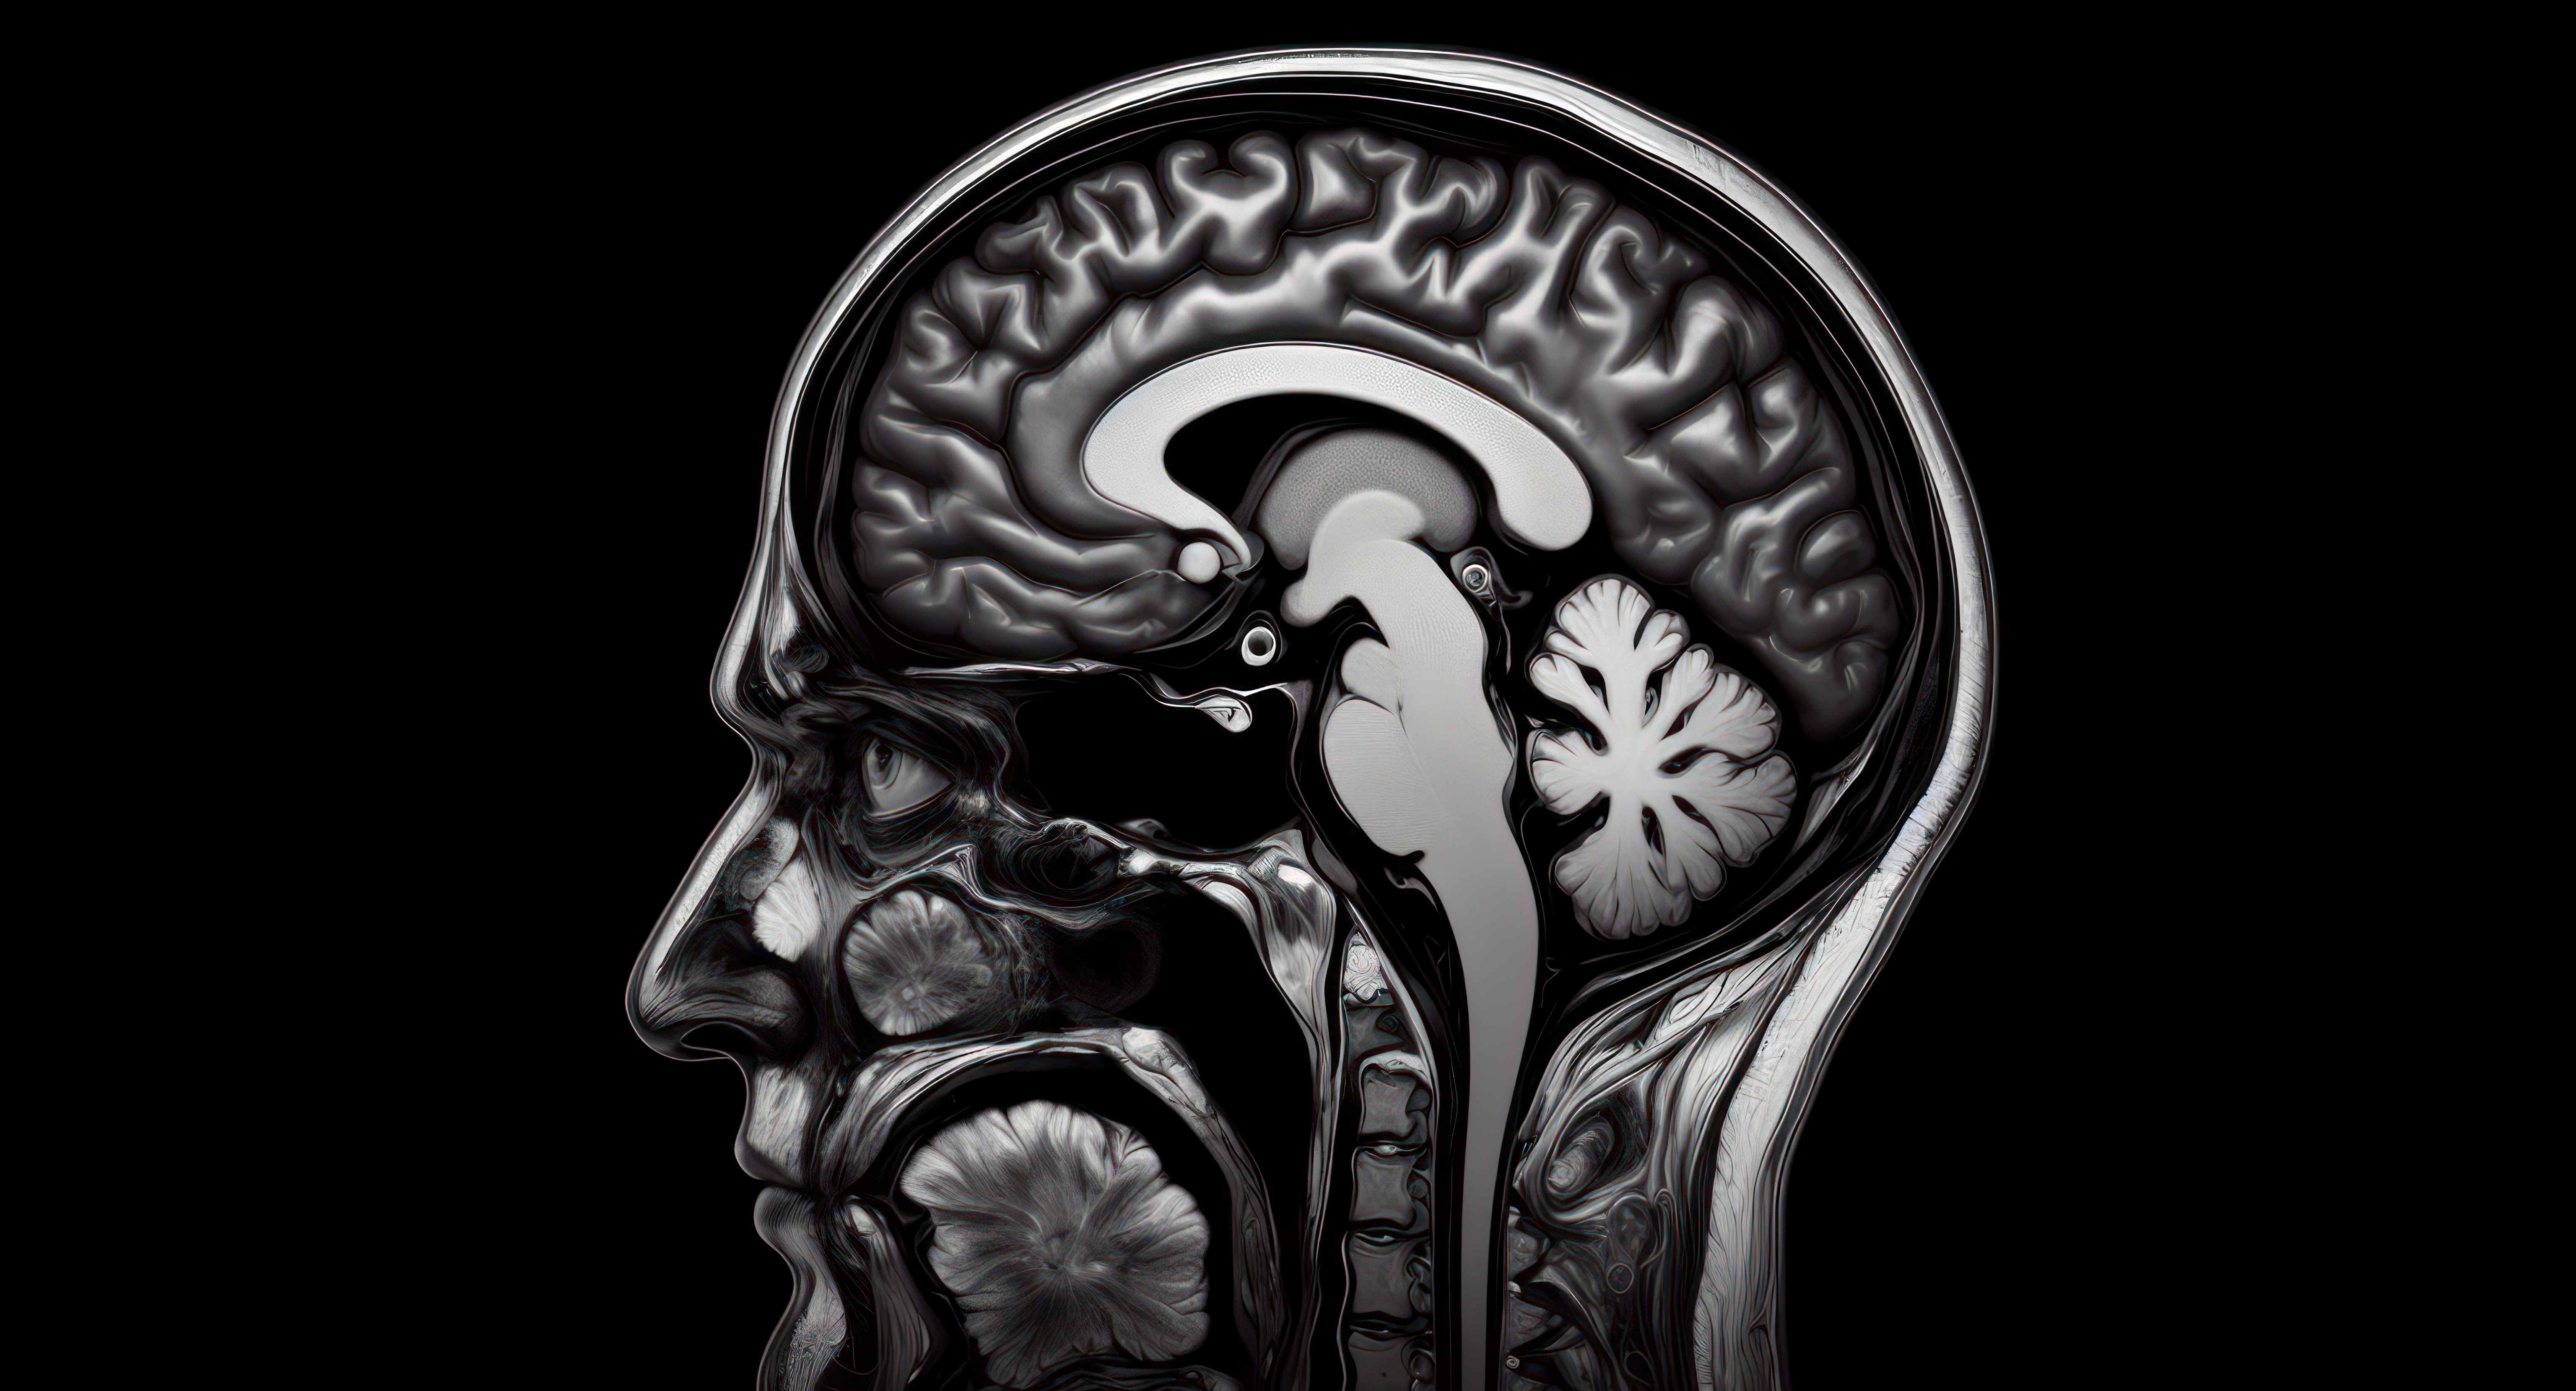

Current MCI detection methods typically rely on MRIs and detailed neuropsychological testing—both of which require trained personnel, extended patient interaction, and significant costs. In contrast, this digital tool provides: